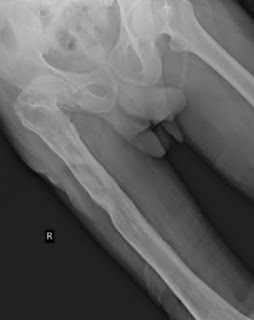

-H/o RTA 3 Years ago after which he got implant in right tibia.

Orthopedic referal taken for stiffness in right knee , chronic Osteomyelitis?,

Opinion of orthopedic:

Extra articular ankylosis

Quadriceps contracture

And suggested for SURGICAL CORRECTION OF QUADRICEPS PLASTY FOR FLEXION OF KNEE